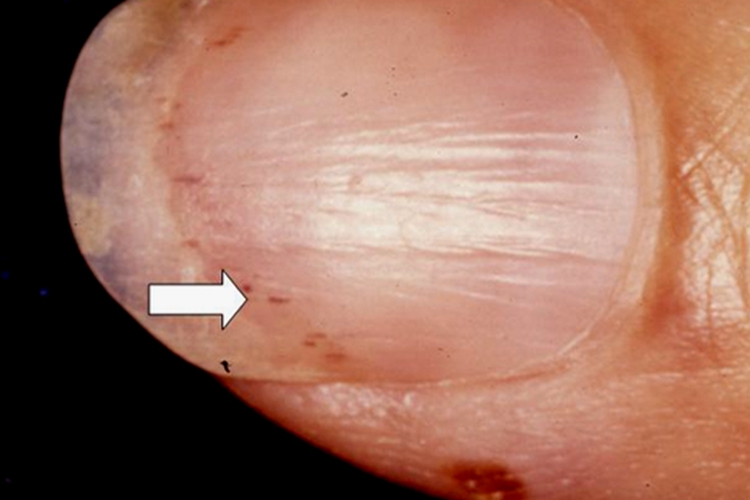

甲乳头状瘤的指甲表现多样,无明显特异性,最常见的临床特征为纵行红甲,也可表现为纵行白甲、黑甲、裂隙状出血,远端甲下局灶性角化性团块、远端甲分离,伴或不伴甲裂隙等。皮肤镜检查可见起源于甲半月均质的纵行条带(红色、白色、黑色),伴条带内含有碎裂出血,甲远端游离缘可见有V形凹口,其下方可见角化性团块。